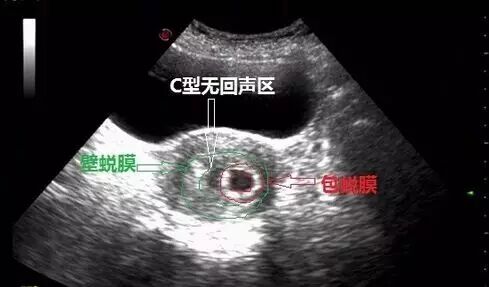

二、双蜕膜征(亦称双环征double-ring sign)

为宫内孕囊与相邻子宫蜕膜结构的断面图像,属于宫内早期妊娠的重要征象。可以用于和异位妊娠的单蜕膜征(单囊征)或假孕囊(pseudo-sac)的鉴别。早孕合并出血时,此征更显著(呈"C"形无回声区),通常预后良好。

双环征妊娠5~8周,妊娠囊周围的高回声绒毛形成内环,外周有一低回声的外环,称双环征。外环可能是包蜕膜与真蜕膜之间的暗区,也有认为外环是由低回声的蜕膜形成,约60%妊娠有此征象。

妊娠囊超声表现中央为暗区(绒毛腔),暗区周边为一完整的、厚度均匀的强回声,这一强回声壁由正在发育的绒毛与邻近的蜕膜组成。随着妊娠囊的增大,它对子宫腔的压迫越来越明显,形成特征性的“双绒毛环征”(Doubledecidual sac sign)或“双环征”。